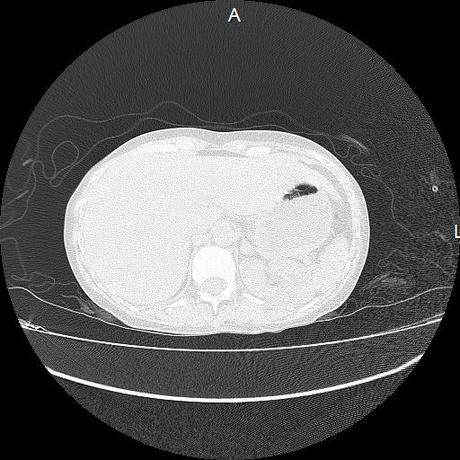

Se realiza volumen de tórax en fase simple, desde los opérculos torácicos hasta los hemidiafragmas, observándose:

El parénquima pulmonar con areas parcheadas difusas en vidrio despulido combinadas con otras areas hipodensas de baja atenuación debidas a atrapamiento aéreo y engrosamiento intersticial y zonas de fibrosis de predominio en lóbulos medios e inferiores de ambos pulmones.

En los cortes valorados de abdomen hígado, bazo y páncreas sin evidencia de alteraciones, glándula suprarrenal izquierda con imagen ovalada, bordes definidos, homogénea, mide 11 mm en probable relacion a adenoma.

- LOS HALLAZGOS PUEDEN ESTAR EN RELACIÓN A NEUMOPATIA INTERSTICIAL PROBABLE ETIOLOGIA HIPERSENSITIVA VS AUTOINMUNE/BACTERIANA/FUNGICA.

- PROBABLE ADENOMA DE SUPRARRENAL IZQUIERDA.